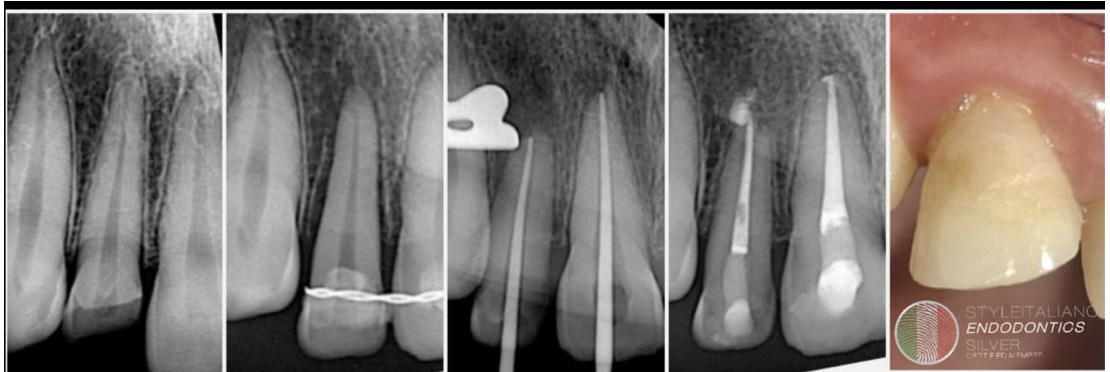

Advances in endodontic materials have influenced contemporary approaches to root canal obturation. A bioceramic sealers possess favorable properties, including biocompatibility, dimensional stability and the ability to form hydroxyapatite, which may enhance sealing root canal spaces. These characteristics have contributed to a shift toward simplified obturation techniques, particularly the single-cone approach. Compared with traditional compaction techniques, this method reduces procedural complexity and clinical time while maintaining an effective seal of the root canal system. For straightforward endodontic cases with adequate cleaning and shaping, simplified obturation protocols using bioceramic sealers have demonstrated predictable clinical outcomes.